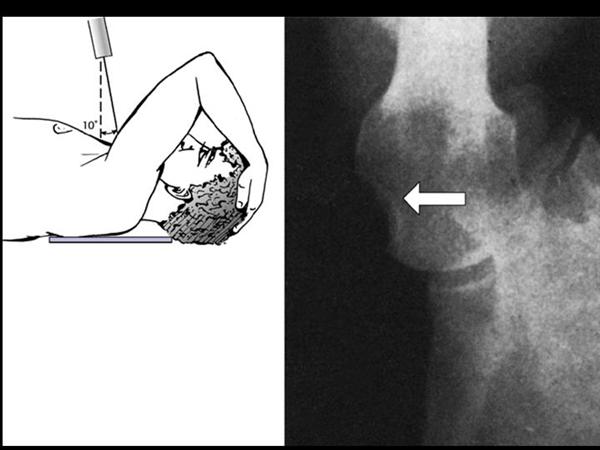

3. axillary lateral view

팔이 안벌어지는 경우에는 velpeau view 를 촬영해 볼 수 있습니다.

상완골의 탈구/아탈구 를 확인해 볼 수 있습니다.